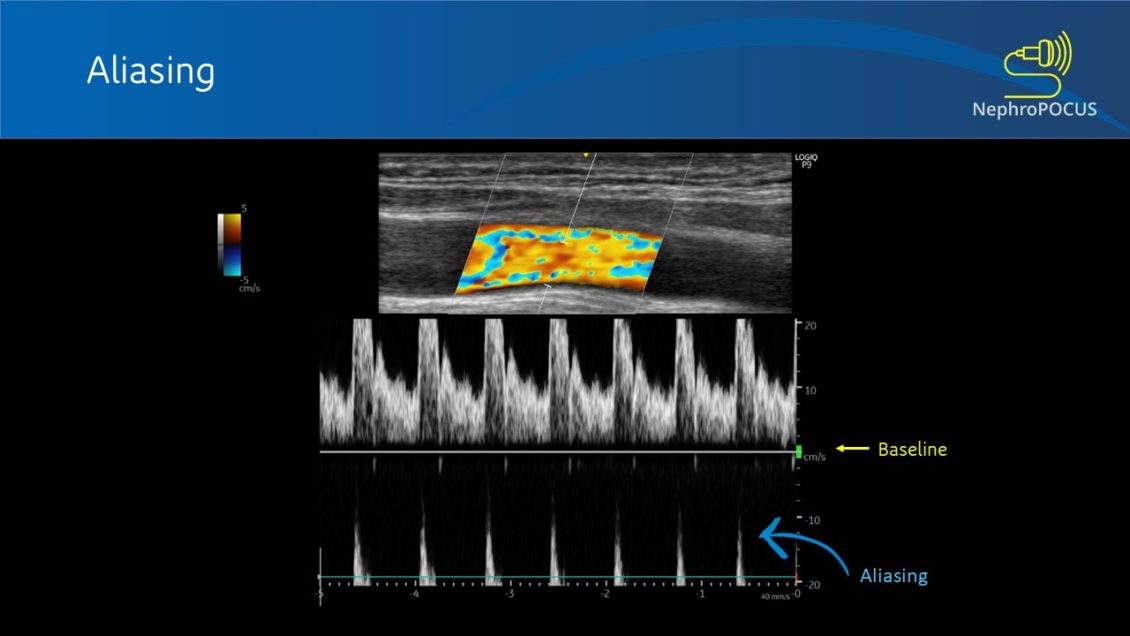

Pulse Wave Doppler Aliasing . Aliasing occurs when the velocity of. Although useful for showing specific structures, pulsed wave doppler is unable to sample at a high enough rate to avoid ‘aliasing’. Although useful for showing specific structures, pulsed wave doppler is unable to sample at a high enough rate to avoid ‘aliasing’. The pulsed wave doppler (pw doppler) sends short pulses of ultrasound and analyzes reflected sound waves between the pulses. Aliasing is a phenomenon in pulsed doppler echocardiography in which when the velocity is beyond a particular limit known as the nyquist limit, the direction of flow is. Increasing the prf/scale will improve the range of velocities able to be displayed by the device. Pwd analyses the doppler shift in a volume sample placed along a sound field line; Unlike continuous wave doppler, pulsed wave and color flow doppler modalities alternate between rapid emission of ultrasound. Aliasing can occur in both color and pulsed wave doppler modes.